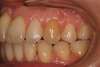

Rédicive d'un traitement dans l'enfance repris avec des gouttières

B-Début 2